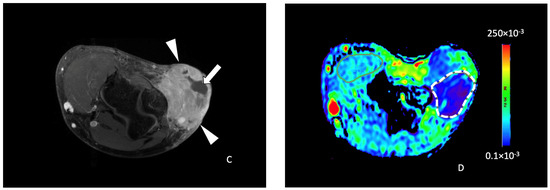

The median ADC value in the STS studied was 134.3 (101.7–167.9) × 10−3 mm2/s. The median tumor-to-muscle ADC ratio was 1.00 (0.77–1.55). There was a significant correlation between the ADC value and the post-treatment tumor necrosis percentage (p = 0.013) with a fair Spearman correlation coefficient (0.47). There was also a statistically significant correlation between the tumor-to-muscle ratio ADC and the post-treatment necrosis percent (p = 0.011) with a 0.48 Spearman correlation coefficient. Among the 20 tumors with less than 50% necrosis after RT, the median ADC value was 120.3 (97.7–161.6) × 10−3 mm2/s (Figure 3), while in tumors with more than 50% necrosis, the mean ADC value was significantly higher: 202.0 (160.9–243.6) × 10−3 mm2/s (p = 0.020) (Figure 4). For tumor-to-muscle ratio ADC, the difference was also significant with median ratios of 0.93 (0.72–1.25) and 1.55 (1.18 to 1.81) for tumors with under and over 50% of histologic necrosis (p = 0.045).

ROC analysis indicated that the ADC value of 161 × 10−3 mm2/s yielded a 95% sensitivity and a 55% specificity for the identification of tumors with more than 50% tumor necrosis ratio after RT (Figure 5). Similarly, a 1.4 tumor-to-muscle ADC ratio cutoff yielded an 85% sensitivity and a 55% specificity.

3.4. DCE Perfusion and Histopathological Analysis

The median tumor-to-muscle AUC ratio in the tumors evaluated was 6.12 (3.52–7.24). MRI parameters are reported in Table 3. Tumor-to-muscle AUC ratios were associated with histologic fibrosis (p = 0.036) with a fair Spearman correlation coefficient (0.41). Tumor-to-muscle AUC ratios in STS with fibrosis grades I, II, and III were 2.65 (2.51–2.69), 5.74 (3.52–6.26), and 6.64 (5.13–8.54), respectively. Tumor-to-muscle AUC ratios were not significantly associated with post-RT necrosis (p = 0.627) nor cellularity (p = 0.502).